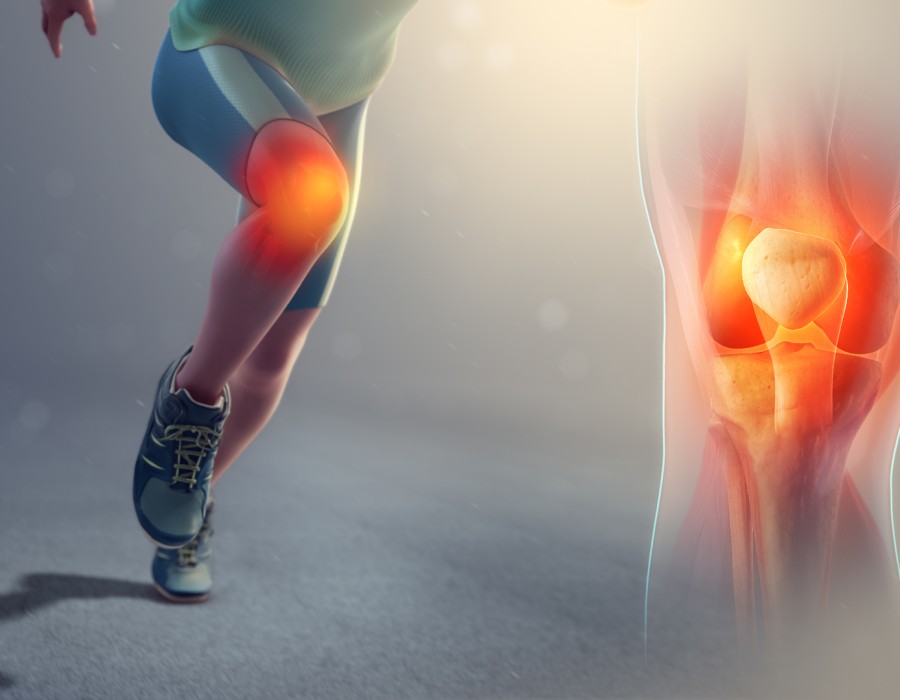

- Clinical Assessment: A skilled sports injury surgeon in Delhi will begin with a comprehensive clinical assessment. This includes a detailed history of the injury, physical examination, and possibly imaging studies such as X-rays, MRI scans, or ultrasound to evaluate the extent and nature of the injury.

- Diagnostic Imaging: Modern sports injury surgeons in Delhi utilize advanced diagnostic imaging techniques to precisely diagnose the injury. This helps in identifying soft tissue damage, fractures, ligament tears, or other structural issues that may require surgical attention.

- Severity of Injury: Certain injuries such as complete ligament tears, severe fractures, or joint dislocations often necessitate surgical intervention to restore function and stability. A sports injury surgeon in Delhi will assess whether the injury is severe enough to warrant surgical repair.